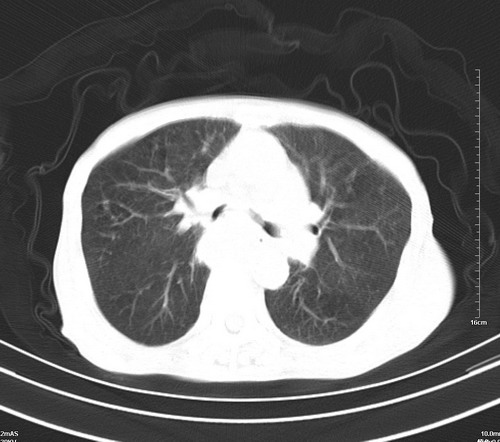

病人,女,79岁,主要因腹疼二月入院,彩超,肝,胆,脾,未见异常,胸透上消化道造影未见异常,化验白细胞增高,内科医生让做胸部ct检查,因为熟人多做了腹部(外科会诊考虑胆囊炎).现ct片如下请假各位战友.

1 气管旁、隆突下淋巴结明显肿大,肝左叶外侧段低密影,都考虑转移。

后中纵隔团块影,伴气管、食道受压移位,首先考虑转移瘤,肝s5段低密度灶。建议增强检查,另外其结肠是否有问题请提供,右肺部分肺叶局限含气增多,考虑局限肺气肿。

后中纵隔淋巴结肿大,首先考虑转移瘤。